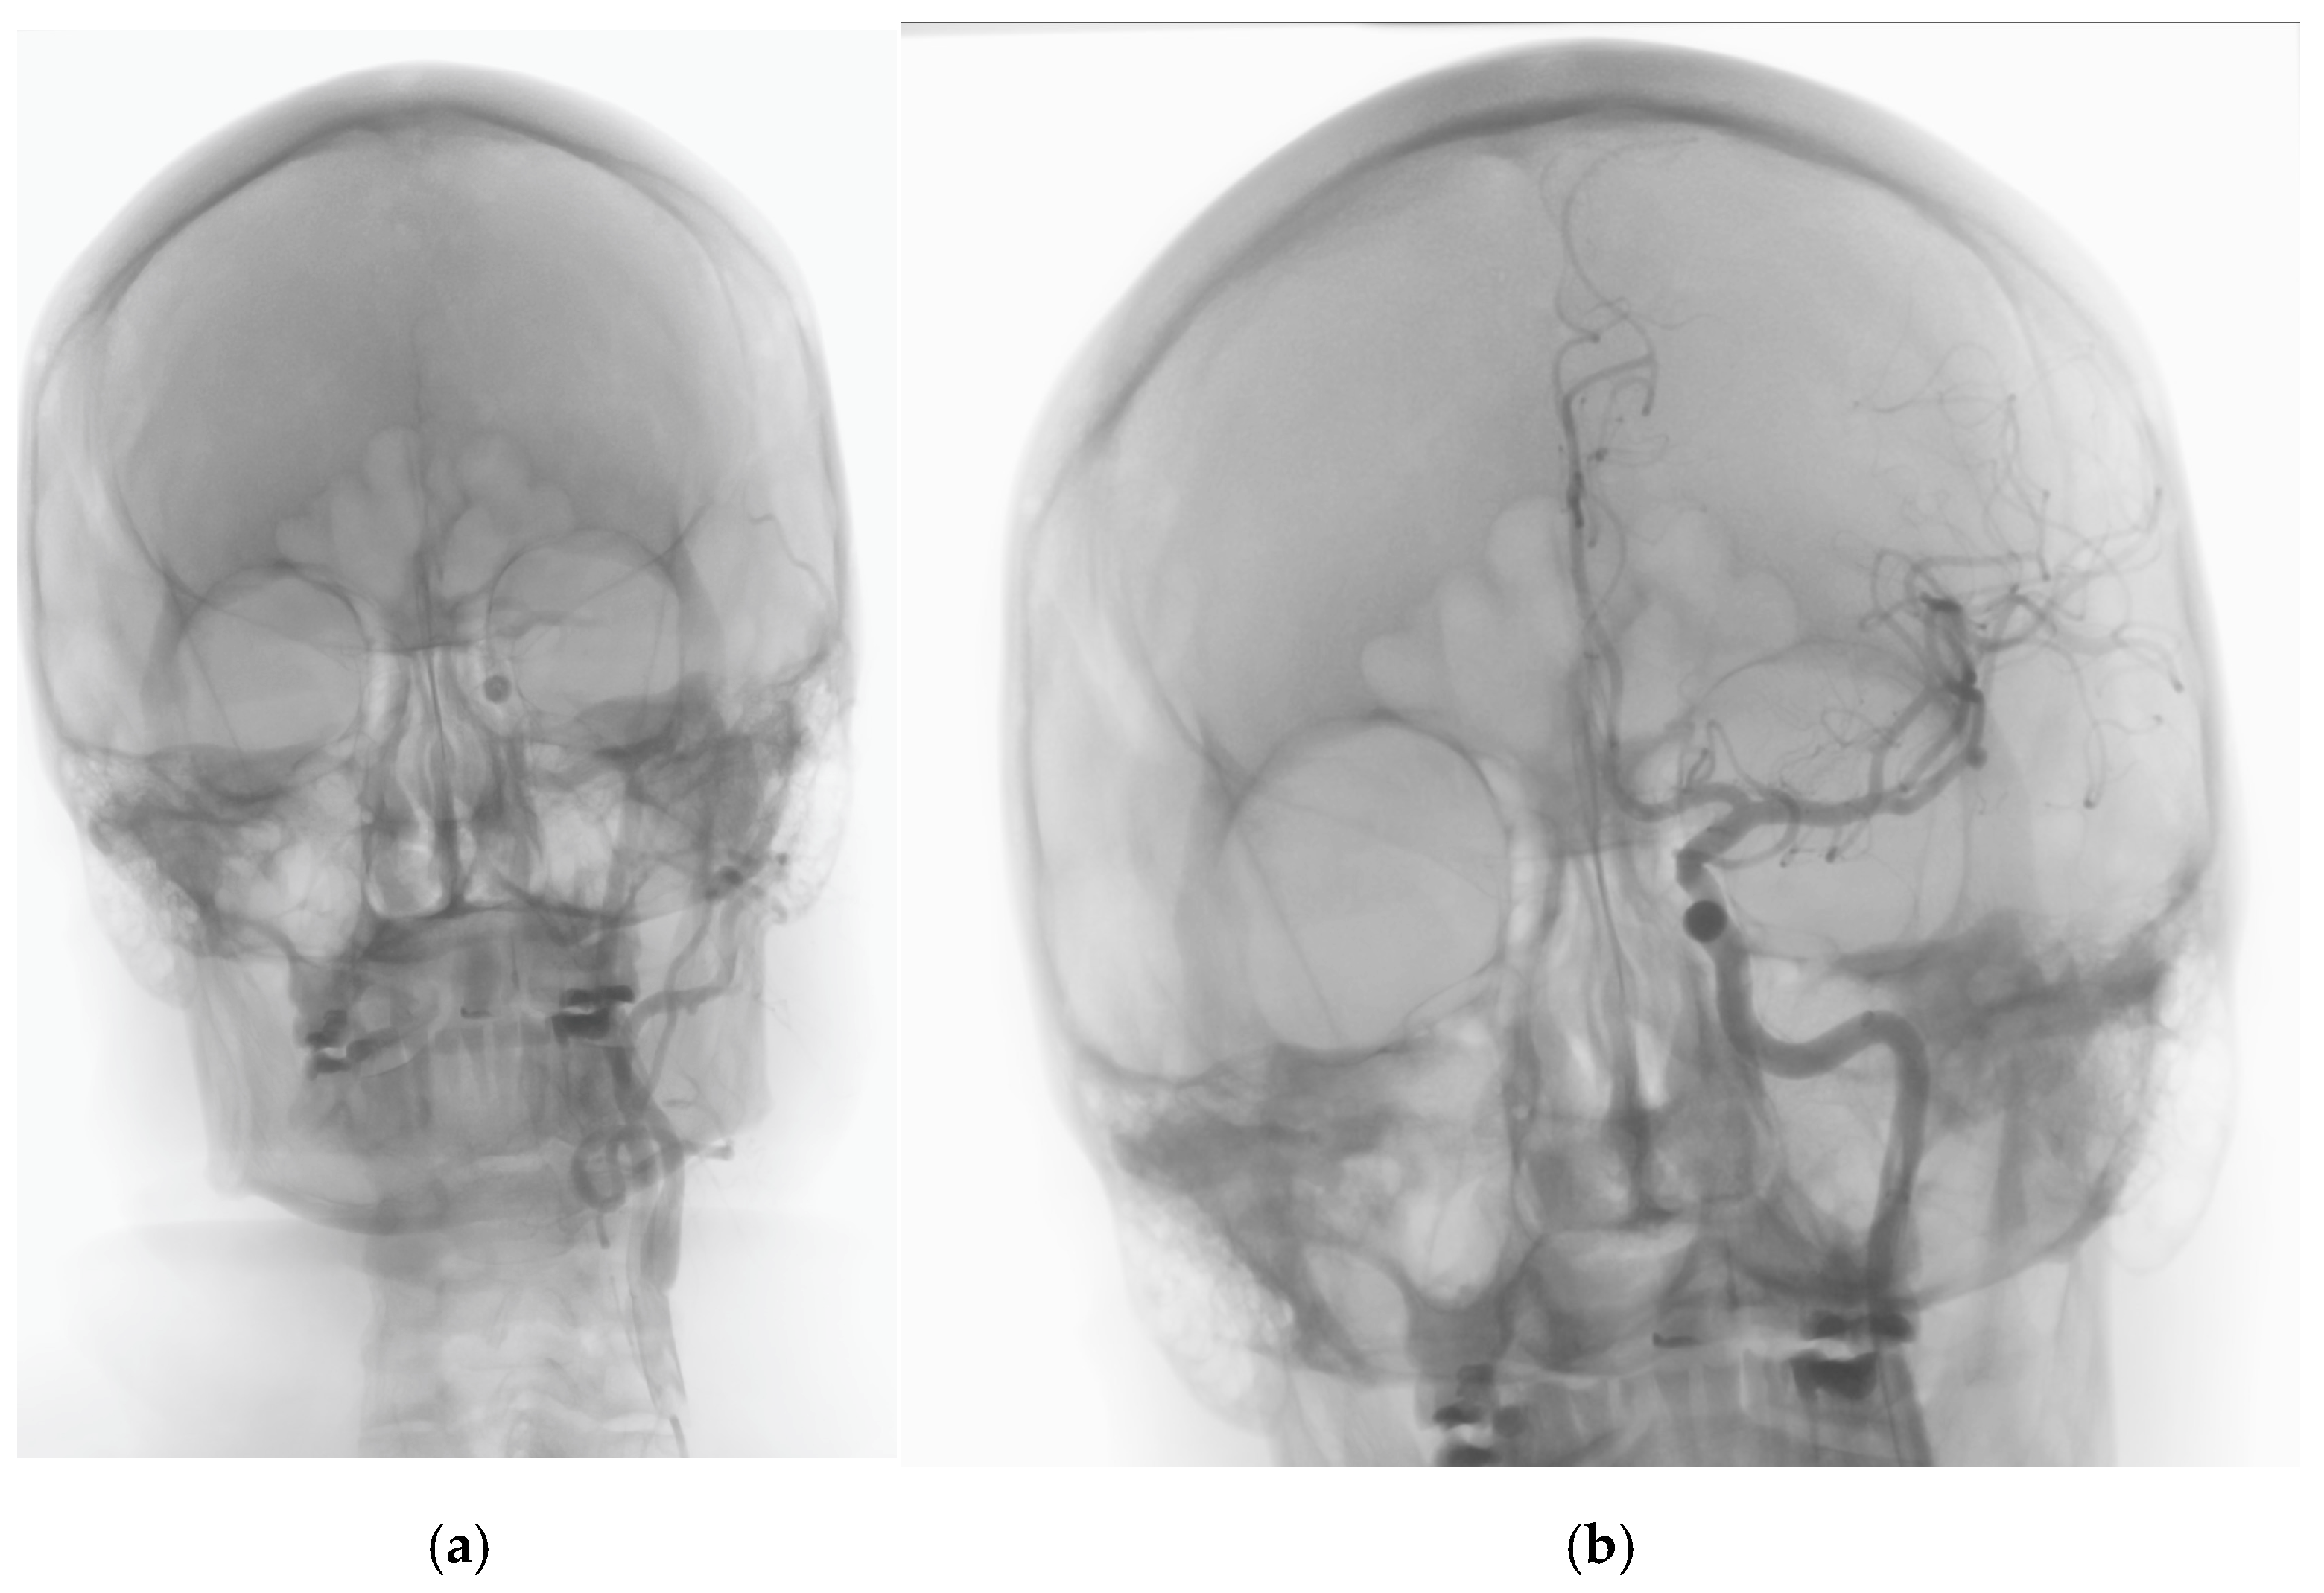

2. Case History